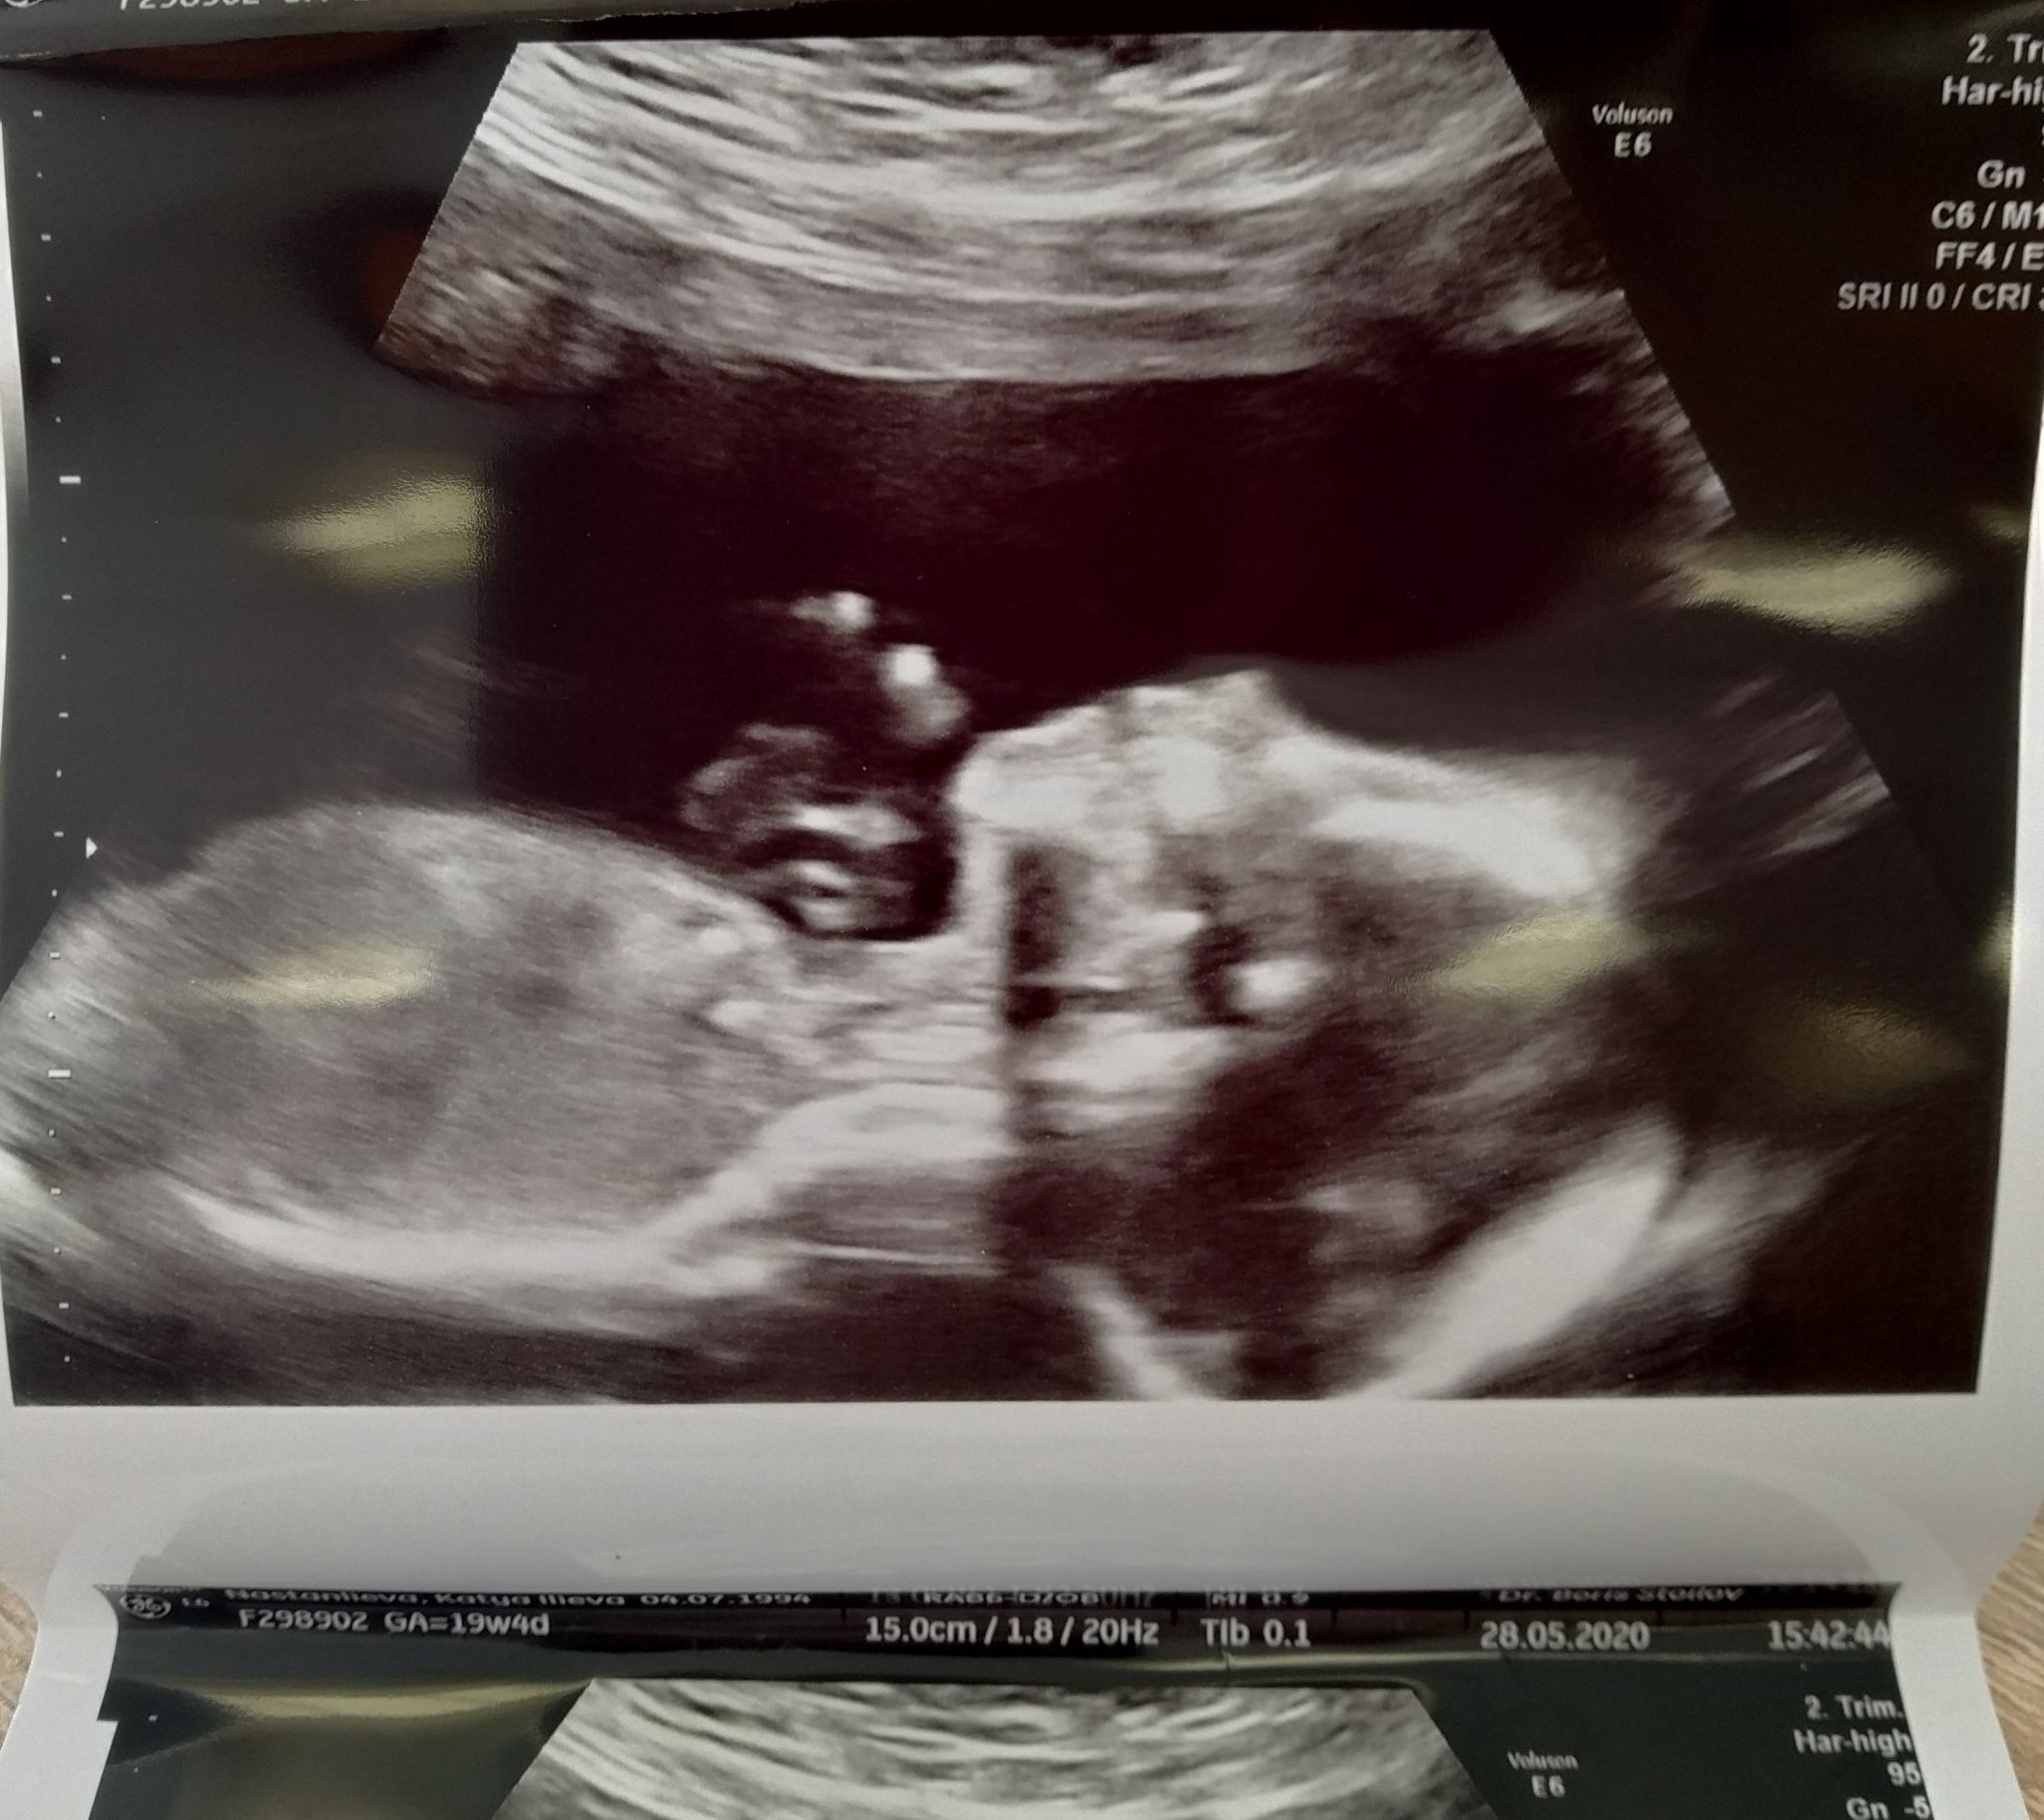

Днес минах на ФМ при д-р Стоилов. Много съм доволна, голям професионалист, любезен и подробен.

Огледа всичко, бъбреци, стомах, мозък, сърце, пръстчета, гръбнак, лице. Бебчо си има всичко. Развива се перфектно.

Тежи 327 гр. Маточната ми шийка е висока и добре затворена, нямам риск от преждевременно раждане. Така ми олекна, че всичко е наред.

И най- голямата новина е, че чакаме момиченце! 🌺